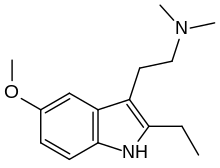

| ST-1936 | artificial | 2-CH3, 5-Cl | CH3 | CH3 | 2-(2-methyl-5-chloro-1H-indol-3-yl)-N,N-dimethylethanamine | 1210-81-7 |